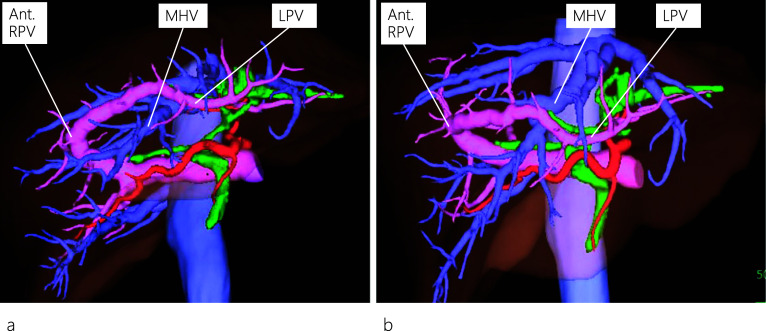

A 45-year-old female patient visited a local hospital with abdominal pain. Blood tests revealed elevated liver enzyme levels, and abdominal computed tomography (CT) revealed dilatation of both the common bile duct (CBD) and intrahepatic bile duct (IHBD). The patient underwent magnetic resonance cholangiopancreatography (MRCP) and endoscopic retrograde cholangiopancreatography (ERCP). MRCP showed CBD stones and stenosis at the confluence of B2 and B3 (Fig. 1a), while ERCP revealed IHBD stones in B2 and B4 (Fig. 1b), which were also observed on abdominal ultrasound (US) (Fig. 1c). Brushing cytology and biopsy at the site of the IHBD stenosis were negative for malignancy. Although the CBD stones were removed, the IHBD stones could not be; therefore, she was referred to our hospital for surgical treatment. Further examination could not be performed around the site of the IHBD stenosis because of impacted stones. Therefore, laparoscopic left hepatectomy was scheduled for suspected intrahepatic cholangiocarcinoma resulting from the impacted stones. However, to properly delineate the anatomy of the liver, enhanced CT was performed, which revealed a dilated IHBD in the left lobe and communication between the right PV and the umbilical portion (Fig. 2a, b). Based on the enhanced CT data, three-dimensional (3D) CT images were reconstructed, which revealed that instead of being located in the left Glisson’s sheath, both the left hepatic artery and bile duct were separated from the left PV (LPV) (Fig. 3a). They also revealed an LPV running through the ventral side of the middle hepatic vein (MHV) (Fig. 3b). Based on these findings, the patient was diagnosed with APB and scheduled to undergo laparoscopic left hepatectomy.

Regarding the anatomy of the bile ducts in patients with APB, Terasaki et al. [ref. 12] reported two patients with different bile duct characteristics, in whom the left hepatic duct ran either inside the liver along the PV or separately down into the common hepatic duct. The differences in running patterns between the PV and the bile duct can be explained from an embryological perspective. In our patient, an ordinary left bile duct was present, and IHBD stones were identified in the dilated B2 and B4. It is noteworthy that on routine preoperative plain CT images, the APB anomaly was not detected owing to the limitation of the images in outlining the detailed anatomy of the liver vasculature. However, the anomaly was detected on the preoperative enhanced CT images, which allowed us to reconstruct 3D images and view the detailed anatomy of the liver vasculature from different positions (neutral and left anterior oblique positions), as shown in Fig. 3.